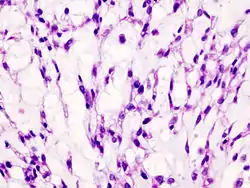

Imaging studies - including radiographs ("x-rays"), computerized tomography (CT), and magnetic resonance imaging (MRI) - are often used to make a presumptive diagnosis of chondrosarcoma.[11] However, a definitive diagnosis depends on the identification of malignant cancer cells producing cartilage in a biopsy specimen that has been examined by a pathologist. In a few cases, usually of highly anaplastic tumors, immunohistochemistry (IHC) is required.

Histopathology